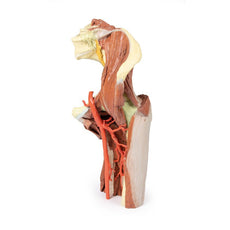

On the right side of the preserved pelvis, the entire femur and thigh musculature has been removed to

demonstrate the obturator membrane, the articular cartilage of the acetabulum and the transverse ligament of the

acetabulum. Posteriorly the entire gluteal region has been dissected to expose the superior gluteal foramen and

the origin of the superior gluteal artery. The sacrotuberous ligament has been removed to demonstrate the